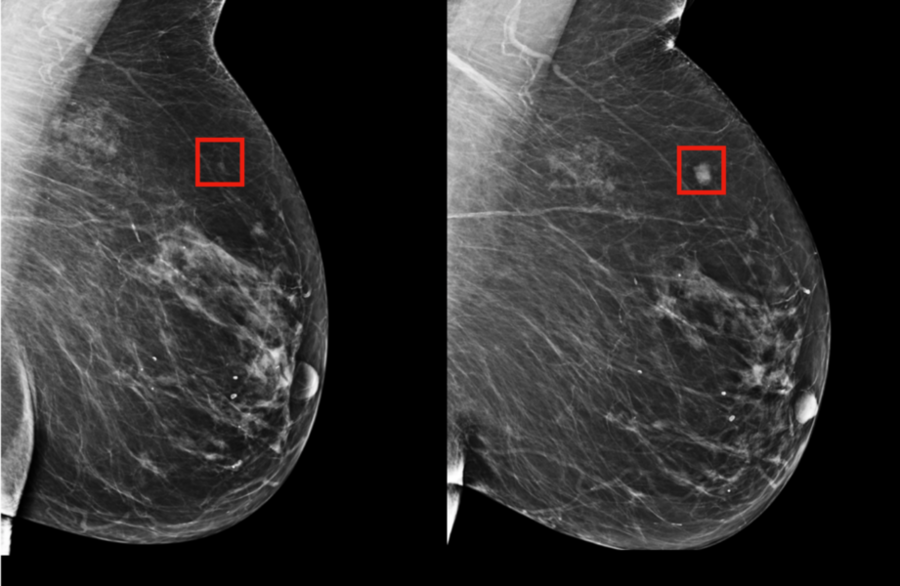

Addressing this critical need, researchers from MIT's Computer Science and Artificial Intelligence Laboratory (CSAIL) in collaboration with Massachusetts General Hospital (MGH) have developed an innovative deep-learning model capable of forecasting a patient's likelihood of developing breast cancer up to five years in advance, using only mammogram data. This sophisticated AI system was trained using mammograms and clinical outcomes from more than 60,000 MGH patients, enabling it to recognize subtle patterns in breast tissue that serve as early indicators of malignant tumors.

Rather than manually identifying patterns in mammograms that might indicate future cancer development, the MIT/MGH team employed a deep-learning model designed to autonomously discern these patterns directly from the data. By analyzing information from over 90,000 mammograms, the AI system successfully detected patterns too subtle for human observation.

"Radiologists have observed since the 1960s that women display unique and highly variable breast tissue patterns visible on mammograms," explains Lehman. "These patterns reflect the complex interplay of genetics, hormones, pregnancy, lactation, diet, and weight fluctuations. Our AI-powered approach enables us to harness this detailed information for significantly more precise individual risk assessments."